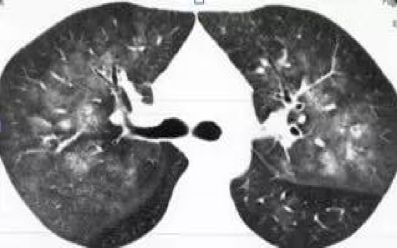

弥漫性的 GGO